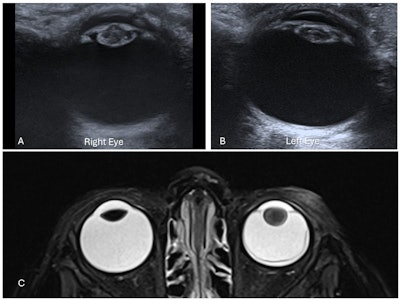

Bilateral coloboma in a 15-day-old neonate with CHARGE syndrome. Ultrasound images of the right eye (A) and left eye (B) show focal defects in the posterior globe with vitreous herniation, suggestive of bilateral colobomas. Axial T2-weighted MR image of the orbits (C) confirms the ultrasound findings. A heavily T2-weighted axial MR image of the petrous temporal bones (D) shows bilaterally dysplastic cochleae and vestibules, with absent semicircular canals -- findings consistent with CHARGE syndrome.